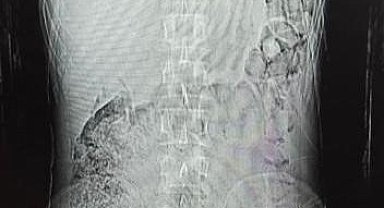

Midesinden 78 kapsül uyuşturucu çıktı